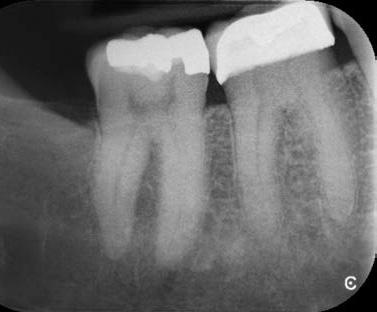

a-m. ábrák: Preoperatív röntgenfelvétel (a) és preoperatív CBCT-felvétel a jobb felső 5-ös (1.5) fogról, sagittalis (b) és axialis (c) nézetek. Az intraorális szkennelés során kapott STL-fájl (d). A 1.5-ös fog navigált endodonciai mikrosebészeti beavatkozásához tervezett sablon (e). A 1.5-ös fog navigált endodonciai mikrosebészeti beavatkozásához nyomtatott sablon (f). Teljes vastagságú mucoperiostealis lebenyt emeltünk (g). A sablont a helyére illesztettük, és a csontablak határait jelöltük (h). A fog gyökerén kívül eső, betört eszköz a 1.5-ös fog periapicalis régiójában (i). Az eltávolított betört eszköz (j). A rezekció, retrográd preparáció és a TotalFill BC RRM Fast Set Putty anyaggal elkészített retrográd gyökértömés utáni röntgenfelvétel (k). A lebenyt varratokkal rögzítettük (l). A kétéves kontroll során készített röntgenfelvétel (m).

Egy 38 éves nőbeteg a korábban kezelt jobb felső második kisőrlőfogából (1.5) kiinduló mérsékelt fájdalom miatt jelentkezett rendelésünkön. A kórtörténetében jelen panasza szempontjából releváns információ nem szerepelt. A beteg a klinikai vizsgálat során vertikális kopogtatásra enyhe érzékenységet jelzett. A kérdéses fog körül mérhető szondázási mélység és a fogmobilitás fiziológiás volt. Periapicalis röntgenfelvételen egy, a fog gyökércsúcsán túl presszálódott betört gyökérkezelő műszerből származó eszközfragmentumot láttunk (2. a. ábra). A preoperatív CBCT-felvétel a buccalis csontlemez épségét igazolta (2. b-c. ábra). A fog revíziója öt hónappal korábban történt. A már előzőleg gyökérkezelt, gyökértömött, majd revideált 1.5-ös fog esetében a diagnózisunk periodontitis periapicalis symptomatica volt. A periapikális elváltozás kezelése érdekében navigált endodonciai mikrosebészeti beavatkozást végeztünk.

A felső állcsontról intraorális szkent (TRIOS) készítettünk, és az ezáltal kapott STL fájlt (2. d. ábra) a CBCT-felvétel során nyert DICOM fájlokkal a Zirkonzahn.Implant-Planner (Zirkonzahn) szoftverben egyesítettük. A sebészi sablont ebben a programban megterveztük, majd a Meshmixer (Autodesk) szoftver se-

gítségével tovább módosítottuk. Az így kapott sebészi sablon egyértelműen meghatározta a periapikális terület eléréséhez szükséges csontablak határait (2. e-f. ábra) Helyi érzéstelenítést követően teljes vastagságú mucoperiostealis lebenyt képeztünk, majd a buccalis csont feltárását követően (2. g. ábra) a sablon segítségével bejelöltük a preparálandó csontablak határait (2. h. ábra). A csontablak kialakítása során Piezotome CUBE LED kézi-darabot alkalmaztunk, majd a leemelését követően a betört eszközt megkerestük (2. i. ábra) és eltávolítottuk (2. j. ábra). A rezekciót ultrahangos megmunkáló fejekkel (ACTEON) végeztük, majd retrográd preparáció következett.

A retrográd gyökértömés elkészítése során TotalFill BC RRM Fast Set Putty-t (FKG) használtunk (2. k. ábra). A lebeny széleit 5/0-s Prolene varratokkal egyesítettük (2. l. ábra). A varratok a műtétet követően 72 órával kerültek eltávolításra. A beteg két évvel később kontrollröntgen készítése céljából érkezett rendelőnkbe. A vizsgálat során a fog tünetmentesnek és funkcióképesnek bizonyult (2. m. ábra).